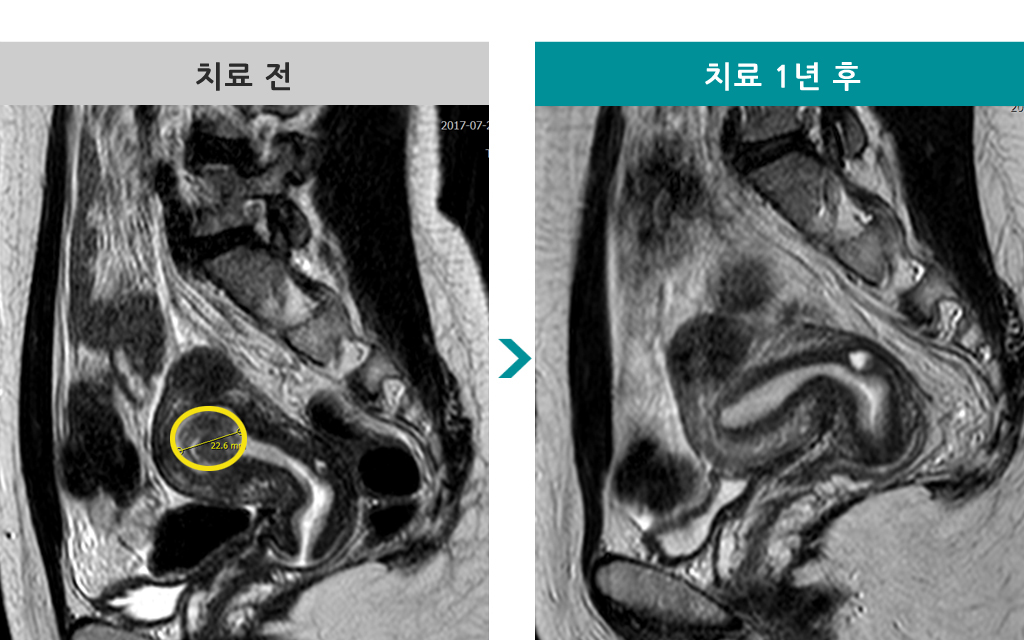

50세 [자궁선근증 색전술] 전후 MRI사진 비교